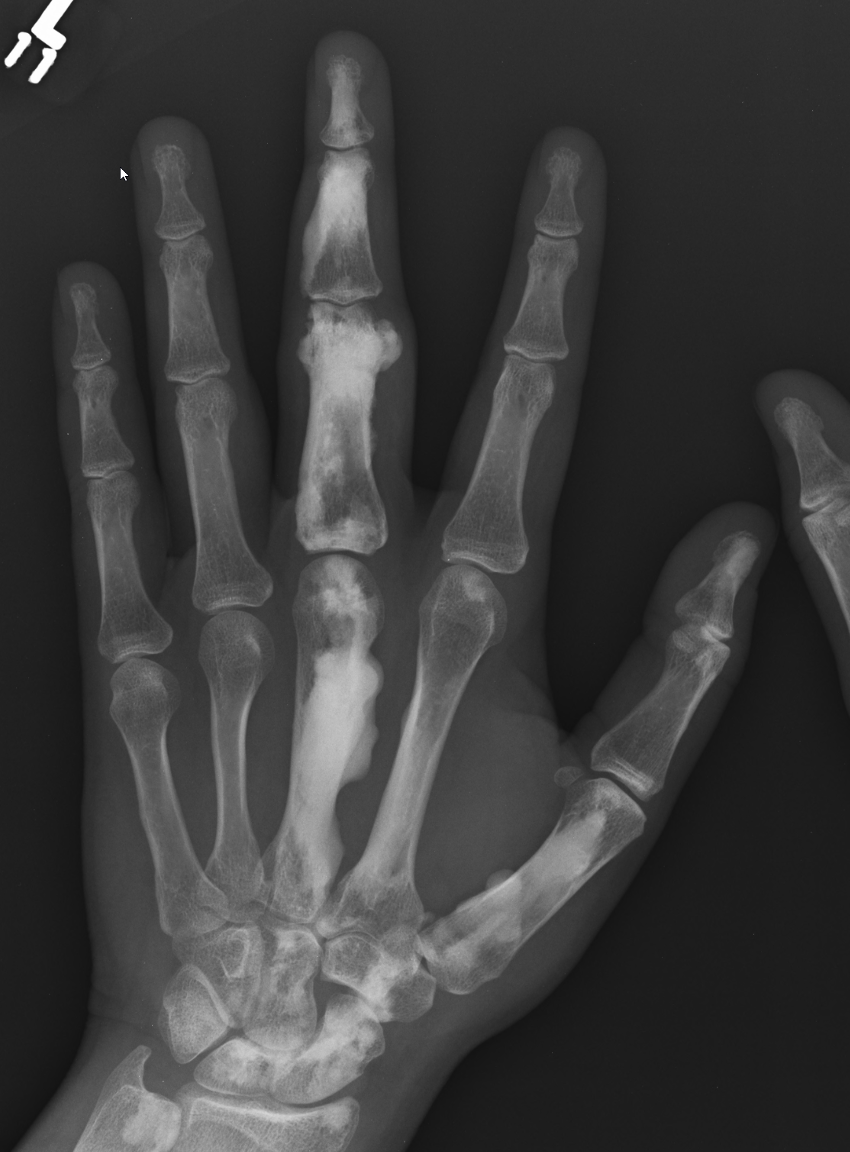

X-ray

Sclerotic lesions of bones

- undulating cortical hyperostosis

- look like wax dripping down the side of a candle

- 33% single bone, 67% multiple bones

- lower limb (67%), upper limb (33%), spine (17%), head (8%)